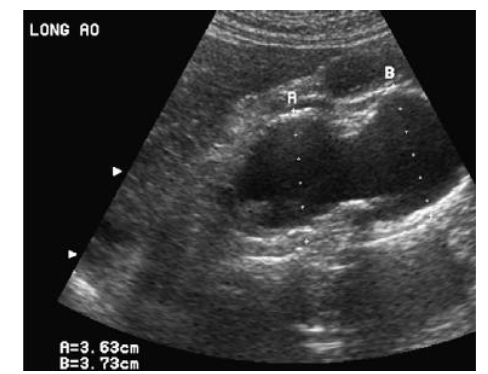

measure aorta

post-stenotic dilation, measure @ ED

be wary in biscuspid bc they have higher dilation and aneurysm risk

Difference between dilation and aneurysm

Aortic aneurysm:

dilatation involving all layers of the aorta 1.5x greater than normal diameter

Aortic dilatation:

diltation involving all layers of the aorta, larger than accepted normal values, but not large enough to be considered an aneurysm

Operation on an aneurysm @ the following levels:

normal patient: 55 mm

bicuspid AoV: 50 mm

Marfan syndrome: 45 mm

OR if growth of aorta is >0.5 cm per year